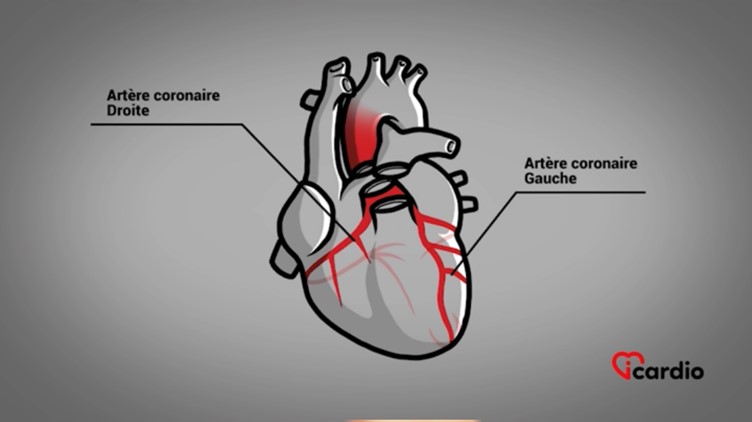

Les artères qui alimentent le cœur

Le réseau sanguin propre à l’alimentation du cœur est composé de 2 artères coronairesLes deux artères coronaires, la droite et la gauche, forment le réseau sanguin qui alimente le cœur en oxygène et en nutriments. Elles sont situées directement à la surface du cœur et se ramifient en branches qui >>, l’une droite et l’autre gauche.